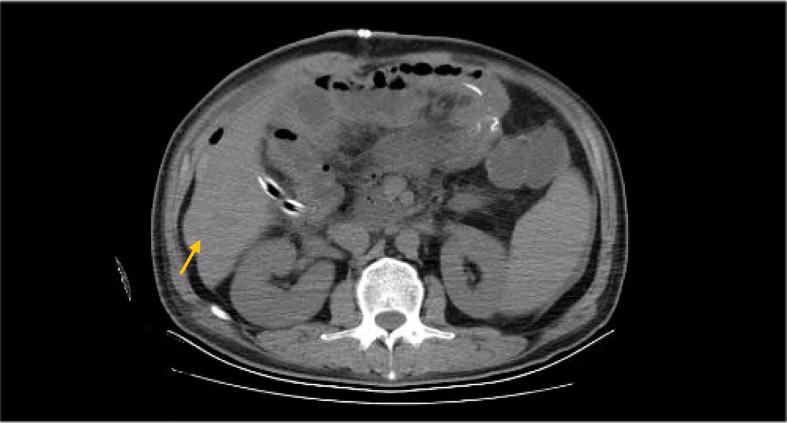

Duodenal adenocarcinoma (DA) is an extremely rare and highly aggressive malignant tumor of the digestive system. Due to the lack of specific clinical characteristics, it is easy to misdiagnosis and miss diagnosis, and the lack of specific consensus and recommendation for treatment, so it often refers to stomach cancer and colorectal cancer. Now, we report a case of a patient with advanced DA who achieved complete remission (CR) after undergoing chemoradiotherapy combined with targeted therapy. The patient was pathologically diagnosed with DA after radical surgery in October 2020, and he failed to undergo adjuvant chemotherapy on time due to the COVID-19 outbreak. The patient found multiple lymph node liver and abdominal metastases 6 months after the operation. Considering the progression of the disease, XELOX regimen (oxaliplatin + capecitabine) chemotherapy was given for 1 cycle. After 1 cycle of treatment, the tumor markers remained elevated; the carcinoembryonic antigen (CEA) was 5.03 ng/ml (0-5 ng/ml), and the carbohydrate antigen 19-9 (CA19-9) was 747.30 U/ml (0-37 U/ml). The patient also developed intolerable capecitabine-related treatment-related adverse events (TRAEs), namely, hand-foot syndrome. For the above reasons, capecitabine was replaced as S-1 at cycle 2, and the chemotherapy regimen became SOX (oxaliplatin + S-1); bevacizumab injection was also added to the SOX regimen, and it was further treated regularly for 7 cycles with the regimen of SOX plus bevacizumab. Liver metastases showed a continuous narrowing trend throughout the treatment period; tumor markers also showed a downward trend. Finally, the patient achieved complete remission (CR) at cycle 7. After completion of chemotherapy, radiotherapy was administered to the resistant metastatic lymph nodes present in the patient's abdominal cavity for a total of 10 times. However, the patient developed severe bone marrow suppression and obstructive jaundice during the course of radiotherapy and finally failed to complete the radiotherapy plan. Currently, the patient continued maintenance therapy with bevacizumab and S-1 and showed no recurrence or metastasis after review. In this case of advanced DA, we referred to both CRC and gastric cancer in the treatment regimen of the patient. At the same time, targeted drugs and radiotherapy were also added to the basis of chemotherapy, which has no clear consensus recommendation or case for reference in the treatment of advanced DA. Thankfully, the patient's disease was controlled and remained stable after treatment with this regimen. Therefore, for patients with advanced DA who lack standardized treatment regimens and guidelines, the combination of chemotherapy with targeted therapy and radiotherapy may be one of the effective treatment modalities.

十二指肠腺癌(DA)是一种极其罕见且侵袭性很强的消化系统恶性肿瘤。由于缺乏特异性临床特征,容易误诊和漏诊,且缺乏针对治疗的特异性共识和推荐,因此常参照胃癌和结直肠癌的治疗。现在,我们报告一例晚期DA患者,在接受放化疗联合靶向治疗后实现完全缓解(CR)。该患者于2020年10月接受根治性手术后病理诊断为DA,因新冠疫情爆发未能按时接受辅助化疗。术后6个月患者发现多发肝淋巴结及腹部转移。考虑到疾病进展,给予XELOX方案(奥沙利铂+卡培他滨)化疗1周期。治疗1周期后,肿瘤标志物仍升高;癌胚抗原(CEA)为5.03 ng/ml(0 - 5 ng/ml),糖类抗原19 - 9(CA19 - 9)为747.30 U/ml(0 - 37 U/ml)。患者还出现了无法耐受的卡培他滨相关治疗相关不良事件(TRAEs),即手足综合征。基于上述原因,第2周期将卡培他滨换为S - 1,化疗方案变为SOX(奥沙利铂+S - 1);SOX方案中还加入了贝伐单抗注射液,并采用SOX加贝伐单抗方案进一步规律治疗7周期。整个治疗期间肝转移灶呈持续缩小趋势;肿瘤标志物也呈下降趋势。最终,患者在第7周期实现完全缓解(CR)。化疗结束后,对患者腹腔内存在的耐药转移淋巴结进行了总共10次放疗。然而,患者在放疗过程中出现了严重的骨髓抑制和梗阻性黄疸,最终未能完成放疗计划。目前,患者继续接受贝伐单抗和S - 1维持治疗,复查后未出现复发或转移。在这例晚期DA病例中,我们在患者的治疗方案中既参照了结直肠癌又参照了胃癌的治疗。同时,在化疗基础上还加用了靶向药物和放疗,在晚期DA治疗中尚无明确的共识推荐或病例可供参考。幸运的是,采用该方案治疗后患者疾病得到控制且保持稳定。因此,对于缺乏标准化治疗方案和指南的晚期DA患者,化疗联合靶向治疗及放疗可能是有效的治疗方式之一。